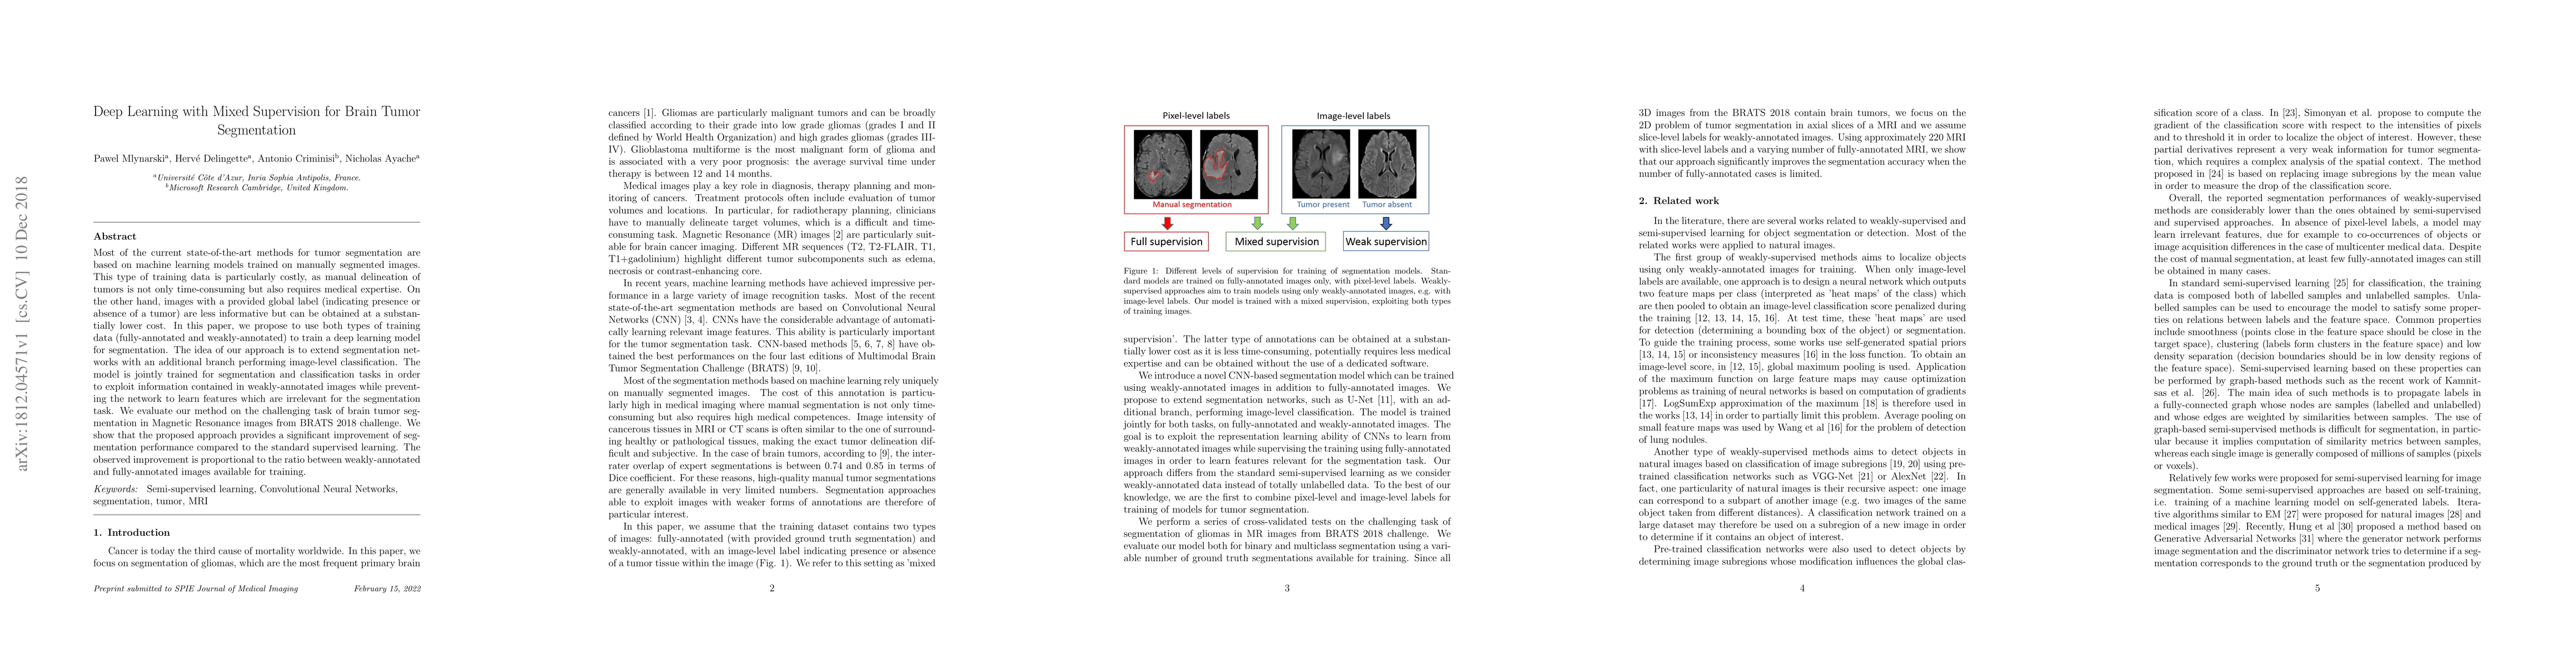

Most of the current state-of-the-art methods for tumor segmentation are based on machine learning models trained on manually segmented images. This type of training data is particularly costly, as manual delineation of tumors is not only time-consuming but also requires medical expertise. On the other hand, images with a provided global label (indicating presence or absence of a tumor) are less informative but can be obtained at a substantially lower cost. In this paper, we propose to use both types of training data (fully-annotated and weakly-annotated) to train a deep learning model for segmentation. The idea of our approach is to extend segmentation networks with an additional branch performing image-level classification. The model is jointly trained for segmentation and classification tasks in order to exploit information contained in weakly-annotated images while preventing the network to learn features which are irrelevant for the segmentation task. We evaluate our method on the challenging task of brain tumor segmentation in Magnetic Resonance images from BRATS 2018 challenge. We show that the proposed approach provides a significant improvement of segmentation performance compared to the standard supervised learning. The observed improvement is proportional to the ratio between weakly-annotated and fully-annotated images available for training.